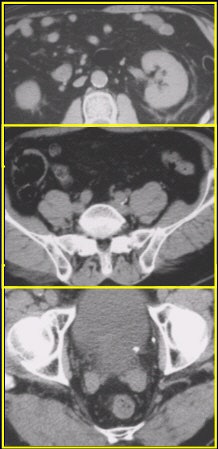

Left ureterovesicle junction stone (UVJ) as seen on the 120-mAs CT scan above and on the 240-mAs scan below.

![]() |